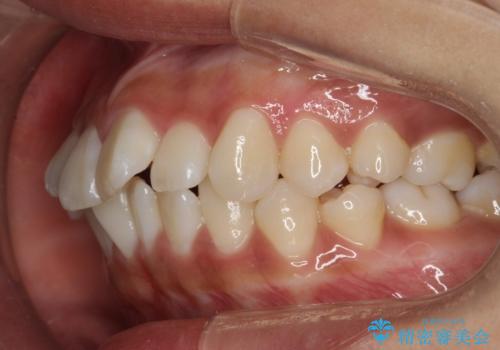

がたがたをインビザラインで整った歯並びへ

- 全体的ながたつきを主訴に来院されました。

抜歯矯正も考えられる状態でしたが、患者様が非抜歯での矯正を希望されたため、歯と歯の間をわずかに削りスペースを作り、全体を整える計画としました。

非常に協力的な患者様でしたので、スムーズに治療を終えることができました。